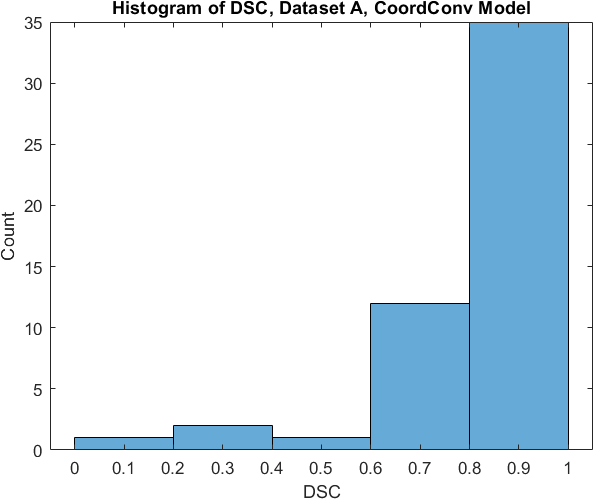

Qualitative prediction results of the two proposed models (baseline nnU-Net and nnU-Net with coordinate convolutions) on the two datasets are shown in Figure 2. Tables 1 and 2 summarise the quantitative performances in terms of DSC and area statistics. Histograms of the DSC values are shown in Figure 3. The median DSCs between the manual segmentations on the subsets of 10 images (i.e. the estimates of inter-observer variability) are also shown in Table 1.

It can be seen that, despite having fewer images, the baseline model for Dataset A obtained a higher median DSC than the model for Dataset B. For Dataset A the coordinate convolution model improved the DSC and reduced the area error and bias. In two-tailed Wilcoxon signed rank tests (0.05 significance) the difference between the baseline DSC and that of the coordinate convolution model was found to be statistically significant for Dataset A () but there was no statistically significant difference for Dataset B (). Interestingly, for both Dataset A and Dataset B, both the baseline and coordinate convolution models performed better than the estimate of inter-observer variability. However, we note that the inter-observer variability is quite high (i.e. median DSCs of 0.78 and 0.71), likely reflecting the difficulty and partly subjective nature of the effusion segmentation task. Therefore, it seems likely that the deep learning models are learning to segment effusion in the style of the main observer, which may not always be consistent with the second observer. In addition, the histograms shown in Figure 3 suggest that there are a significant number of failure cases in the outputs of both models (although fewer for the coordinate convolution model for Dataset A), again reflecting the difficulty of the task.